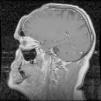

El Pott's puffy tumor (PPT) es una rara entidad que en la actualidad representa un abombamiento del cuero cabelludo asociado a un absceso subperióstico y a una osteomielitis craneal, pudiendo acompañarse o no de infección intracraneal. Suele asociarse a la sinusitis frontal, tratándose de una complicación típica, aunque poco frecuente de la misma. Por su parte las osteomielitis causadas por Actinomyces son raras y suelen tener lugar a nivel mandibular, no encontrándose apenas casos de osteomielitis craneal causada por este género bacteriano, en especial tras traumatismo craneoencefálico. Presentamos un caso especialmente poco usual al tratarse de un PPT frontal tras traumatismo cerrado, con componente intracraneal y en el que tras cirugía se aisló Actinomyces como copartícipe de dicha infección, junto con Fusobacterium y Propionibacterium.

Pott's puffy tumour (PPT) is a rare entity that involves scalp swelling associated with subperiosteal abscess and cranial osteomyelitis, occasionally accompanied by intracranial infection. It is usually affiliated with frontal sinusitis, which is a typical but infrequent complication. On the contrary, Osteomyelitis by Actinomyces is rare and usually occurs at the mandibular level, with very few cases of cranial osteomyelitis caused by this bacterial specie, especially after traumatic brain injury. We report an exceptionally unusual case of a PPT frontal tumor after blunt trauma (closed head injury), with an intracranial lesion whereby Actinomyces was isolated after surgery, as a co-participant of the mentioned infection besides Fusobacterium and Propionibacterium.